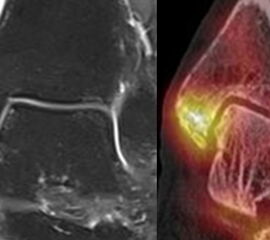

Abbildung 2.3.

Klärung bei Schmerzen im rechten OSG bei OCL an der medialen Talusschulter. Z. n. OSG-Distorsion vor 2 Jahren und Z. n. OSG-Fraktur / Syndesomosenruptur. Ausgedehnte OCL, hier jedoch kein erhöhter Knochenmetabolismus; lediglich Nachweis einer Stressreaktion im Bereich der Synchondrose eines Os trigonum als Schmerzursache.

Zum Lesen der Bildbeschreibung und zur Vollansicht bitte das Bild anklicken. Bild: H. C. Rischke